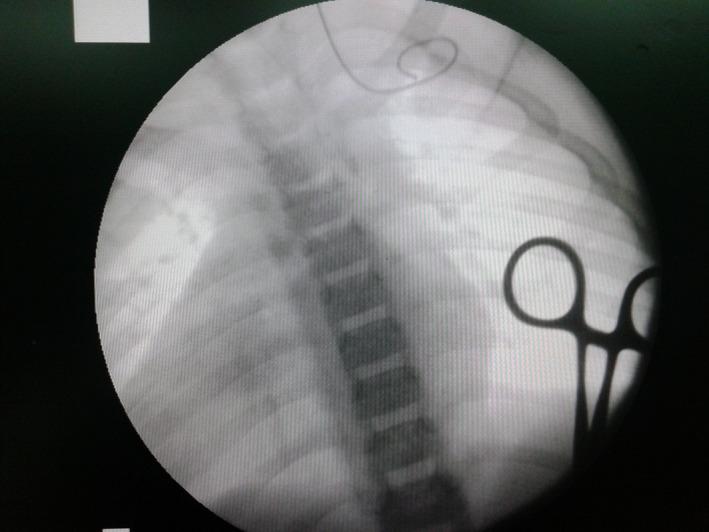

Patients with genetic disorders are potentially more susceptible to present vascular abnormalities compared to the general population. For these patients, unusual difficulties could appear during a CVC placement procedure that could lead to major complications if venous abnormalities are undiagnosed. Ultrasound and fluoroscopy guidance should be used routinely for all patients in order to avoid complications and catheter misplacement.

与普通人群相比,患有遗传性疾病的患者可能更容易出现血管异常。对于这些患者,在中心静脉导管(CVC)置入过程中可能会出现异常困难,如果静脉异常未被诊断出来,可能会导致严重并发症。为避免并发症和导管误置,所有患者都应常规使用超声和荧光透视引导。